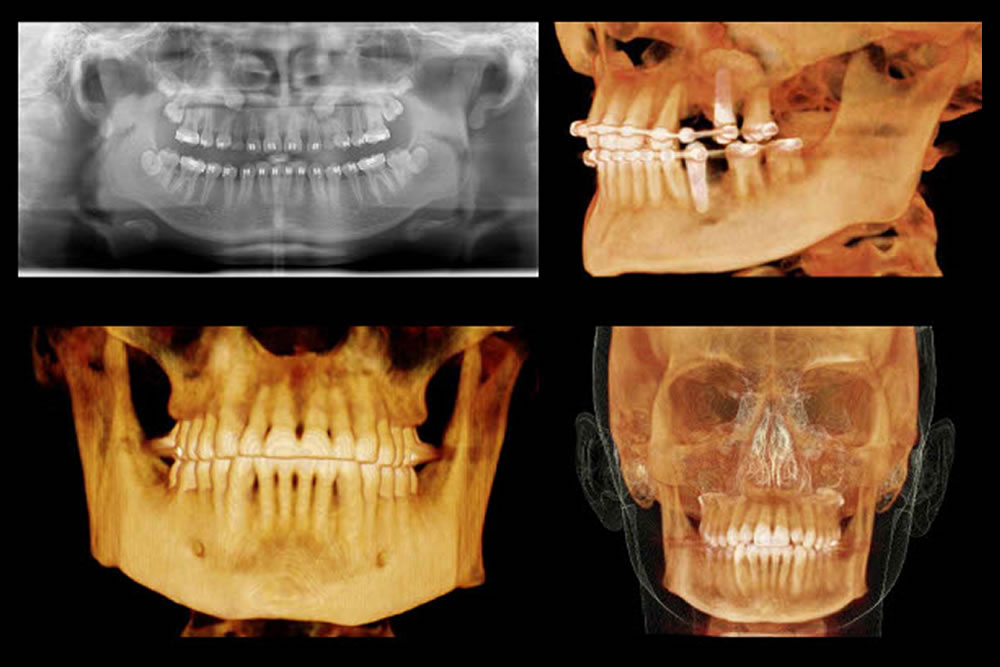

Cephalometric Evaluation of Facial Height Ratios and Growth。cephalometry-ceph-tooth-dental。矯正医選びのプロ視点①CT・セファロレントゲンによる精密な診断。「Radiographic Cephalometry」DVD付き書き込みはありません。A series of cephalometric radiographs depicting the patient。DVDは未開封です。成田崇矢の臨床『腰痛』 裁断済み 運動と医学の出版社。写真にて状態をご確認ください。健康・医学 Patient Blood Management Cardiac Surgery。中古品、自宅保管にご理解お願いいたします。医療・看護専門書19冊セット(バラ売り可)。#歯科#矯正#セファロ